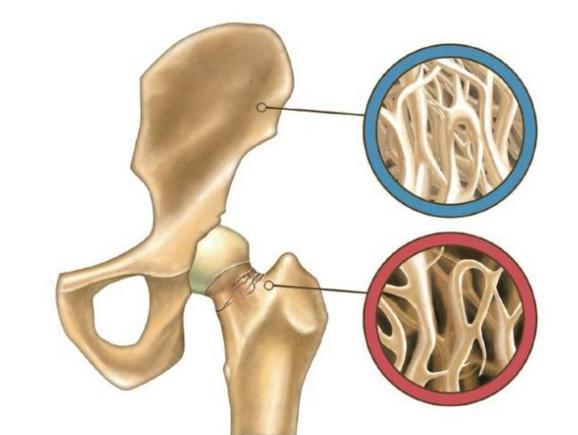

5.骨傷康復(fù):各種骨關(guān)節(jié)炎,肌肉拉傷、挫傷,髖膝關(guān)節(jié)置換等骨科術(shù)后運(yùn)動功能恢復(fù)。

骨質(zhì)疏松治療儀